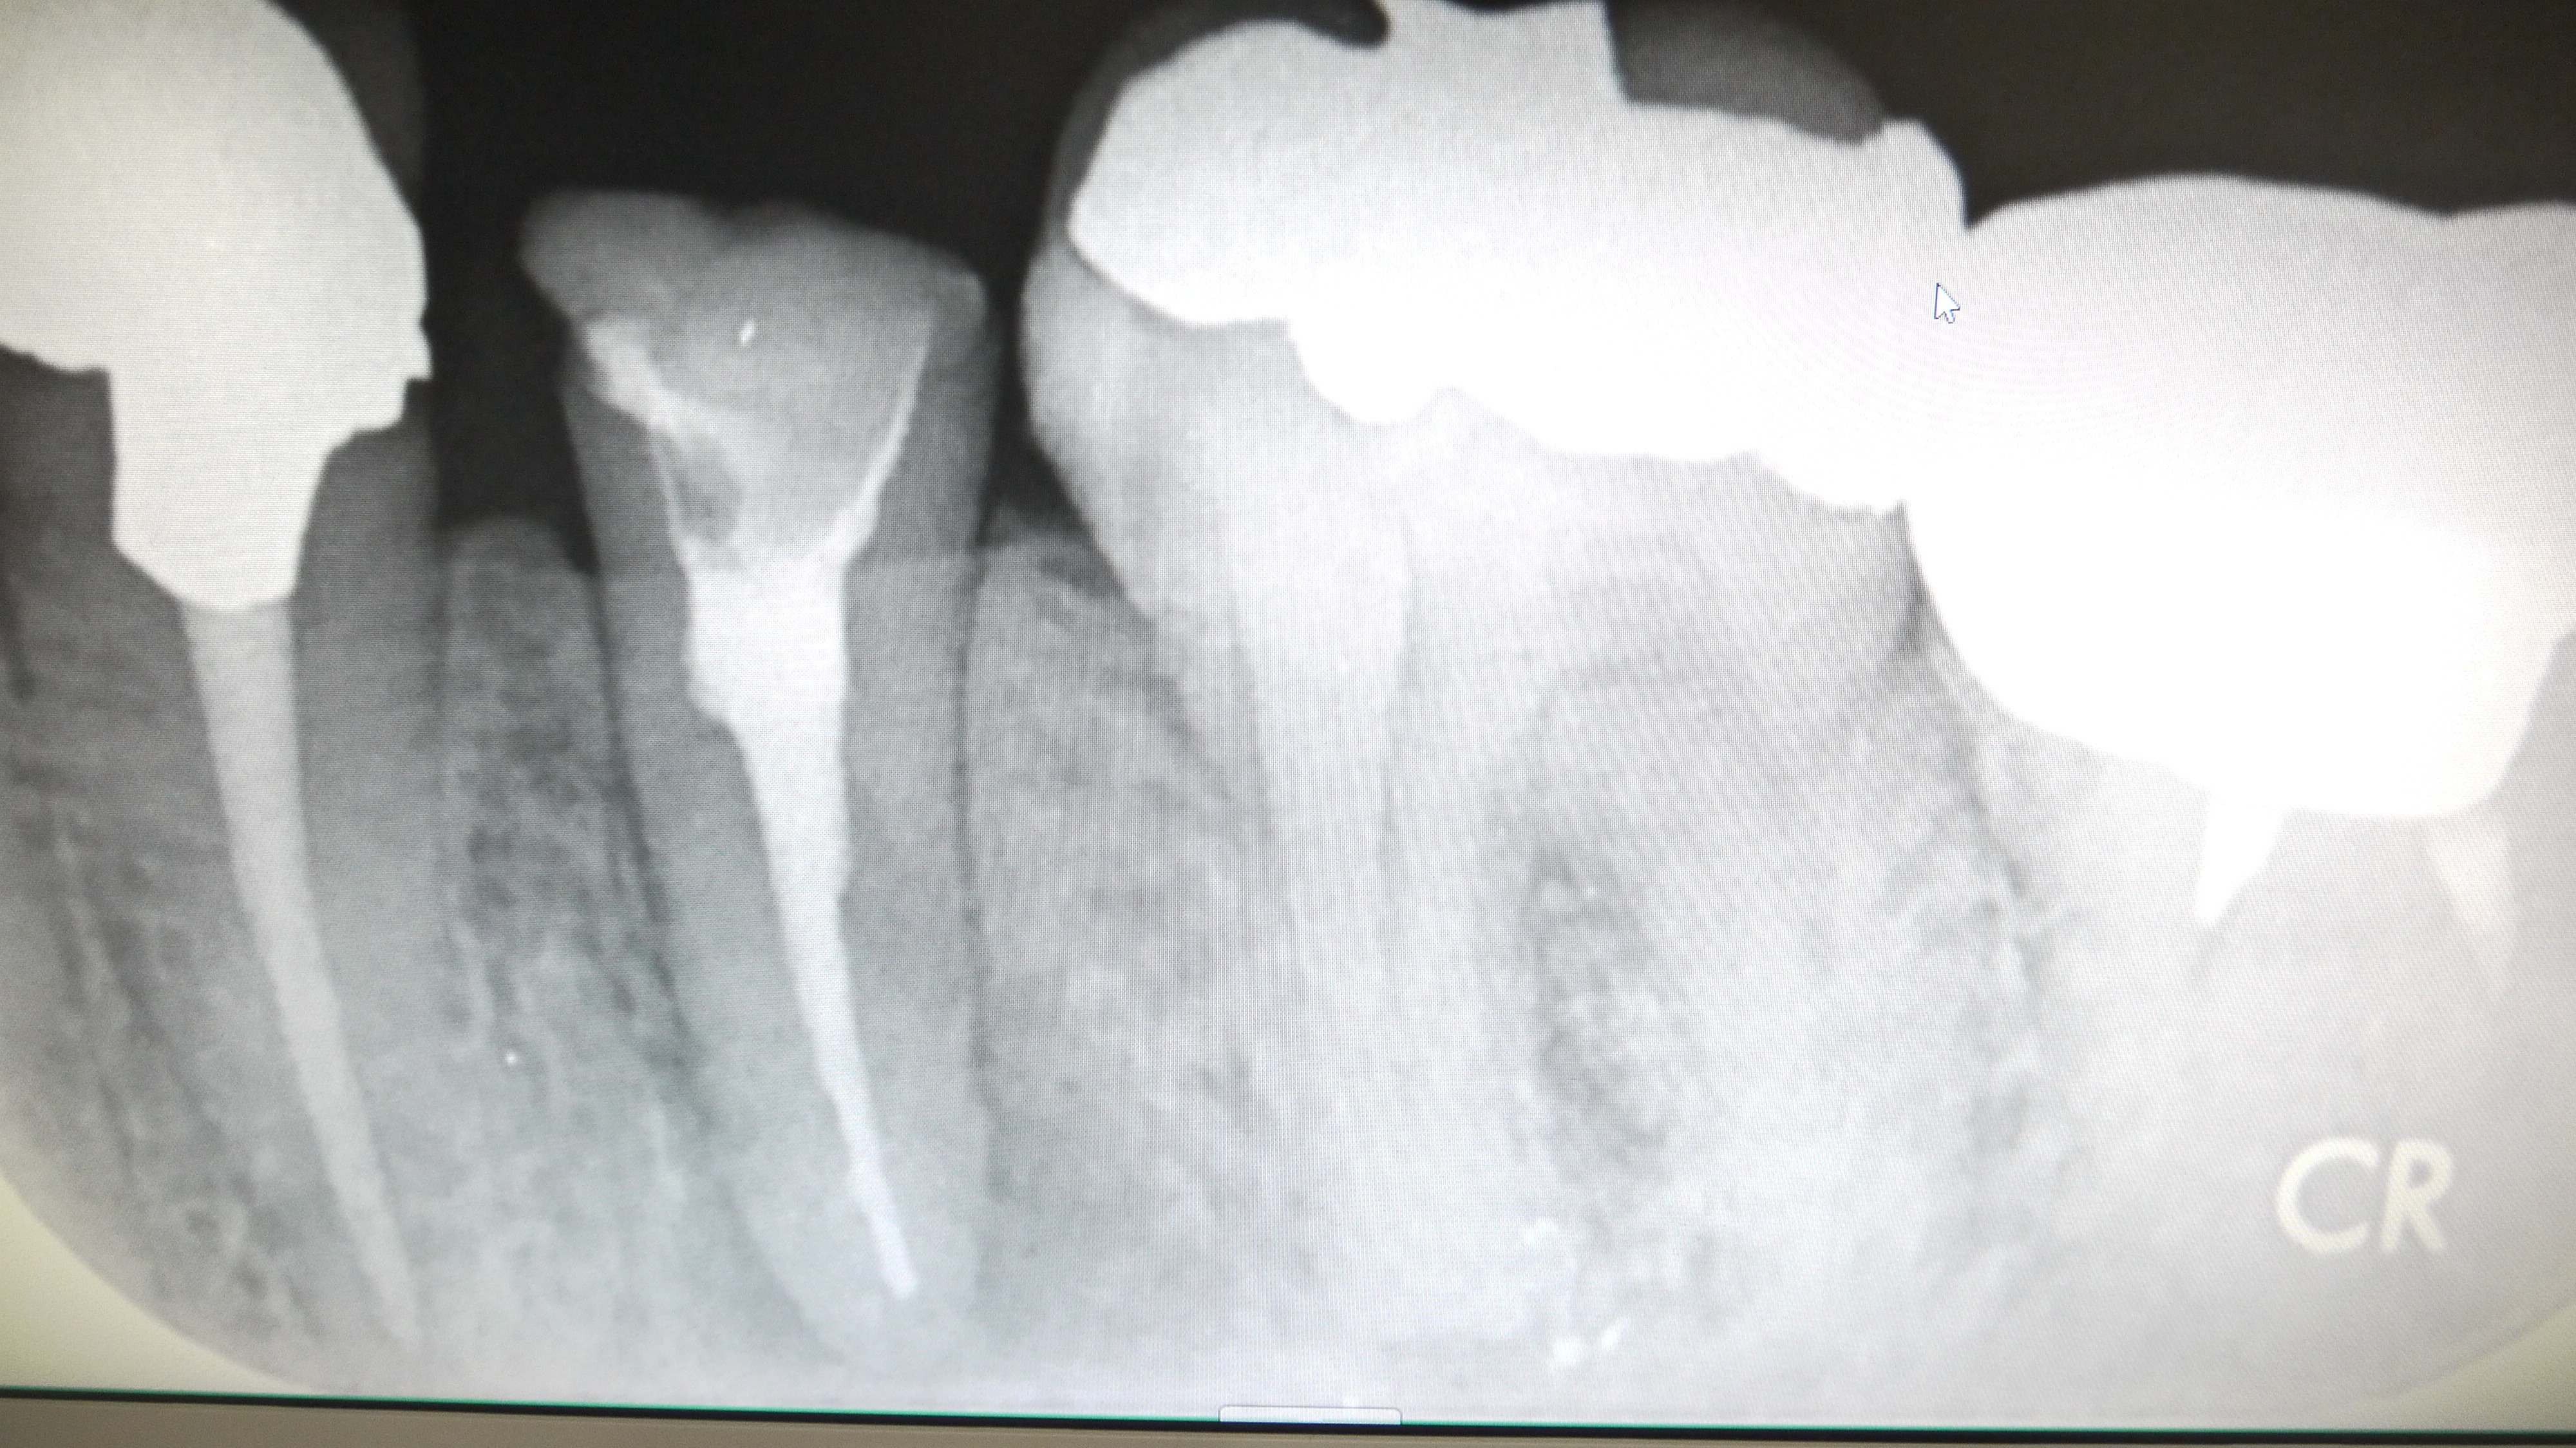

根管の中に薬(ガッタパーチャとシーラー)をつめていきます。(根管処置)

この際、根の長さぴったりまで加圧しながら薬を詰めていくことが

腫れの再発を防ぐために最も重要です。